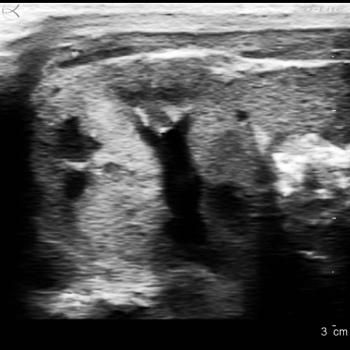

Case History: 49-year-old female presented with palpable right breast retroareolar mass.